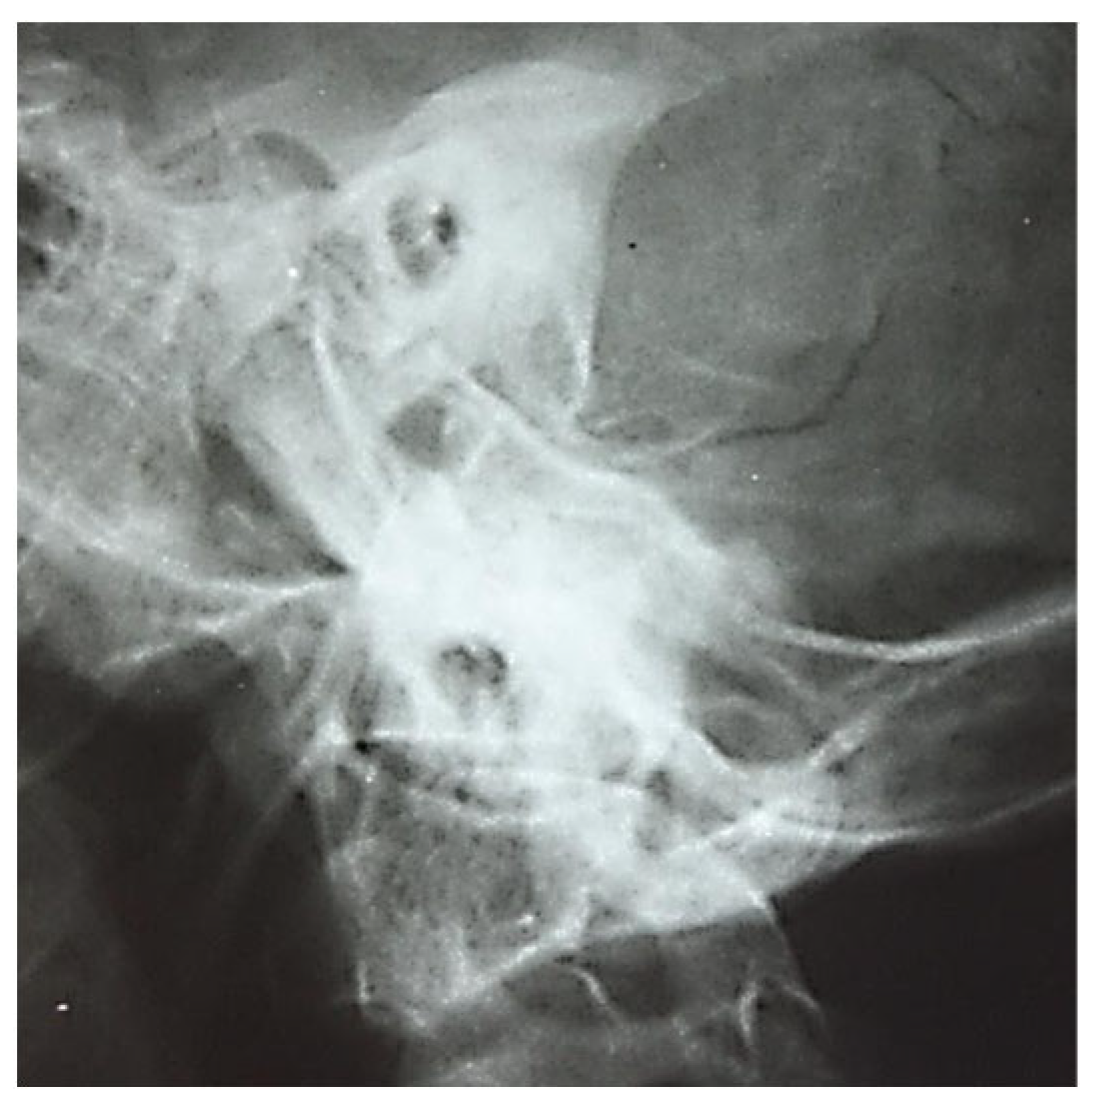

3.1.1. Conventional Radiology

3.1.2. Computed Tomography and Magnetic Resonance Imaging